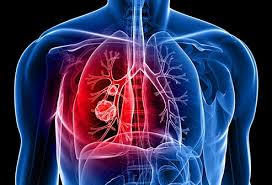

How Did My Cat Get Lung Cancer : Cancer In Cats Elwood Vet : Lung cancer survivors may get too many pet scans.. The same drugs used to treat human cancer patients are used in cats too, only in smaller doses. I spent about 3 hours researching on the. Squamous cell carcinoma and bronchioalveolar carcinoma are other types of cancer that occur in cat lungs. While cancer in cats is not as common as it in dogs, it is still one of the leading causes of death in older cats. Causes of lung cancer a clear cause for lung cancer hasn't been discovered yet.

Cancer In Cats Symptoms Treatment Purina from www.purina.co.uk Primary lung cancer originates in the lungs, while secondary lung cancer spreads to the lungs from some other part of the body. Like other malignant tumors, adenocarcinoma of the lungs is usually seen in older animals (more than ten years). As i mentioned, the virus felv can cause cancer in cats. Chemotherapy uses drugs to treat cancer. The commonest types of cancer affect the white blood cells, the skin and the breast. Bad breath may indicate oral cancer, although it's also a symptom of a sinus infection. With the advent of virus testing, vaccination against felv and selective breeding, the cancer caused by this virus has diminished greatly. The same drugs used to treat human cancer patients are used in cats too, only in smaller doses.

This type of carcinoma is relatively rare in cats, with no known breed disposition. The commonest types of cancer affect the white blood cells, the skin and the breast. Probably $500 to $1,000 to do the initial diagnostic testing. With the advent of virus testing, vaccination against felv and selective breeding, the cancer caused by this virus has diminished greatly. The clinical signs of lung cancer can vary. As i mentioned, the virus felv can cause cancer in cats. Lung cancer in felines can be primary, when the cancerous tissues have developed in the lung area first, or secondary, when the disease has spread from another part of the body. (that and the blood work showed no increase/decrease in wbc count) the vet feels certain it is cancer and referred me to a specialist for a definitive diagnosis. Primary lung tumors and metastatic lung tumors. Best no dust cat litter. Lymphoma is by and large the most common cancer that affects cats, although there are other types of feline cancers that can affect domestic cats. Adenocarcinoma grows rapidly and metastasizes to distant parts of the body and organs, including the brain, eyes, bones, and lymph nodes. The number of cases of primary lung tumors in cats has increased in recent years, though the exact reason for the increase is unknown.

Cancer in cats is the leading cause of death among cats. About 20 to 30 years ago, this virus led to cancer development in young cats (2 to 5 years old). Feline lung cancer causes and symptoms Many cancer symptoms in cats are subtle and can be caused by another condition, but if you notice any of the following potential. Cat lung cancer can be one of two types, either primary or secondary. Hi, i normally hang out on the colorectal cancer board, but my cancer has spread to my lungs, so i wanted to share what i found out about cat litters, because i decided to find the best litter to avoid inhaling the dust that all the popular clay clumping litters can cause. Primary lung tumors and metastatic lung tumors. Those that do may have difficulty breathing (labored or rapid breathing, even while resting), reduced ability to manage walks (exercise intolerance), decreased appetite, weight loss, coughing or sneezing (with or without discharge. We gave my cat an injection for antibiotics and steroids to help her symptoms through the. Bad breath may indicate oral cancer, although it's also a symptom of a sinus infection. Other tumors (e.g., malignant melanoma) most often spread to the lungs, which act as a filter for tiny cancer cells. Then it costs anywhere from $800 to $2,000 for surgical approaches. Lymphoma is by and large the most common cancer that affects cats, although there are other types of feline cancers that can affect domestic cats.